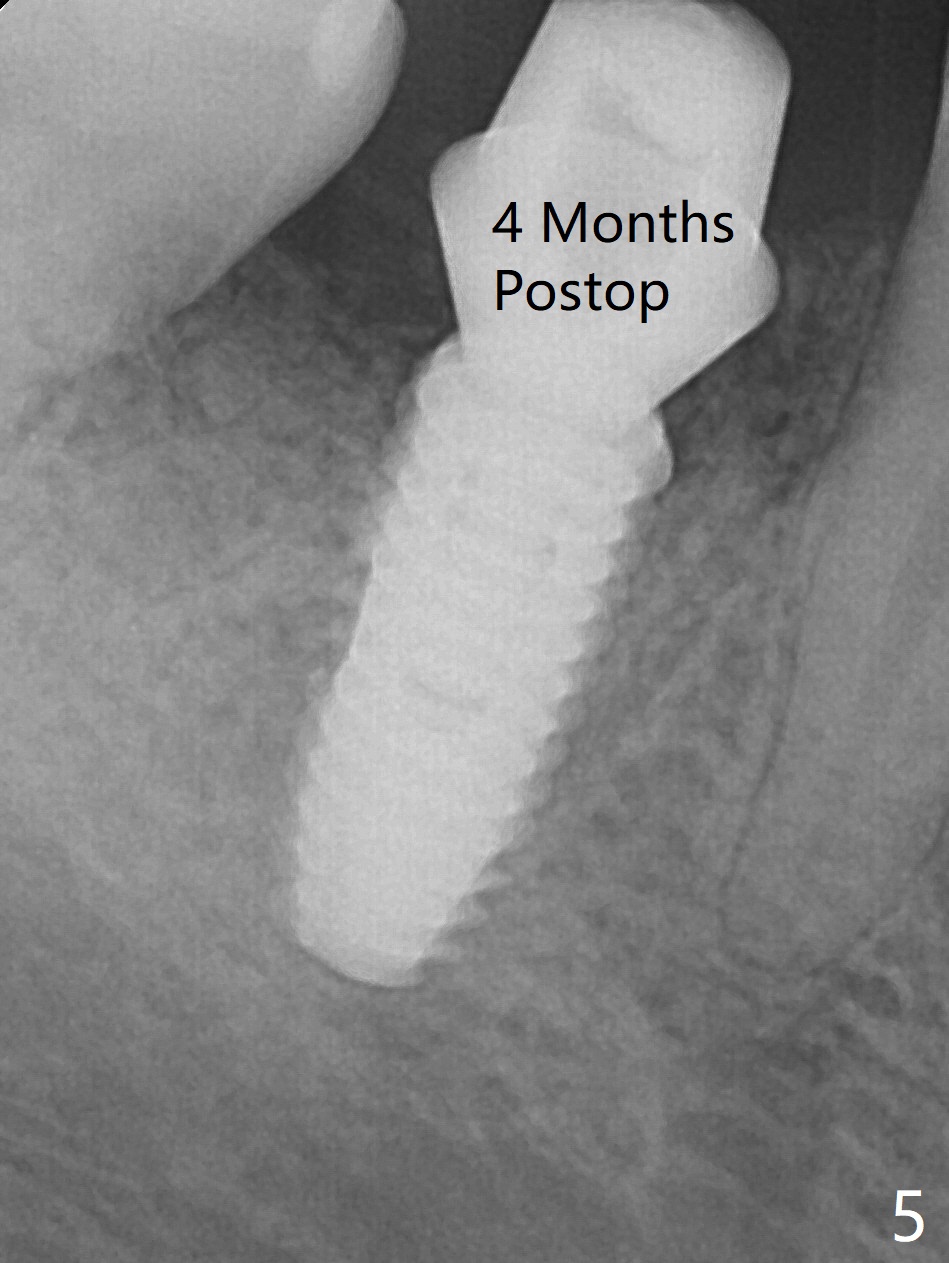

After extraction of #30 (Fig.1 (S: septum)), a 5x11.5 mm implant is placed with guide mainly in the mesial socket (mesial to the septum (S) with >35 Ncm; after immediate placement of a 6.5x4(3) mm abutment, allograft is placed (Fig.2 *). An immediate provisional is fabricated to hold the bone graft in place (Fig.3 P). To prevent micro-movement, the provisional has clearance from the opposing dentition (Fig.4 *, nonfunctional). There is not too much loss of bone graft 4 months postop (Fig.5). In fact the mesial and distal sockets heal. The implant plateau is covered with the bone 8 months post cementation (Fig.6 arrowheads ( *: addition of porcelain for the distal gingival embrasure)).